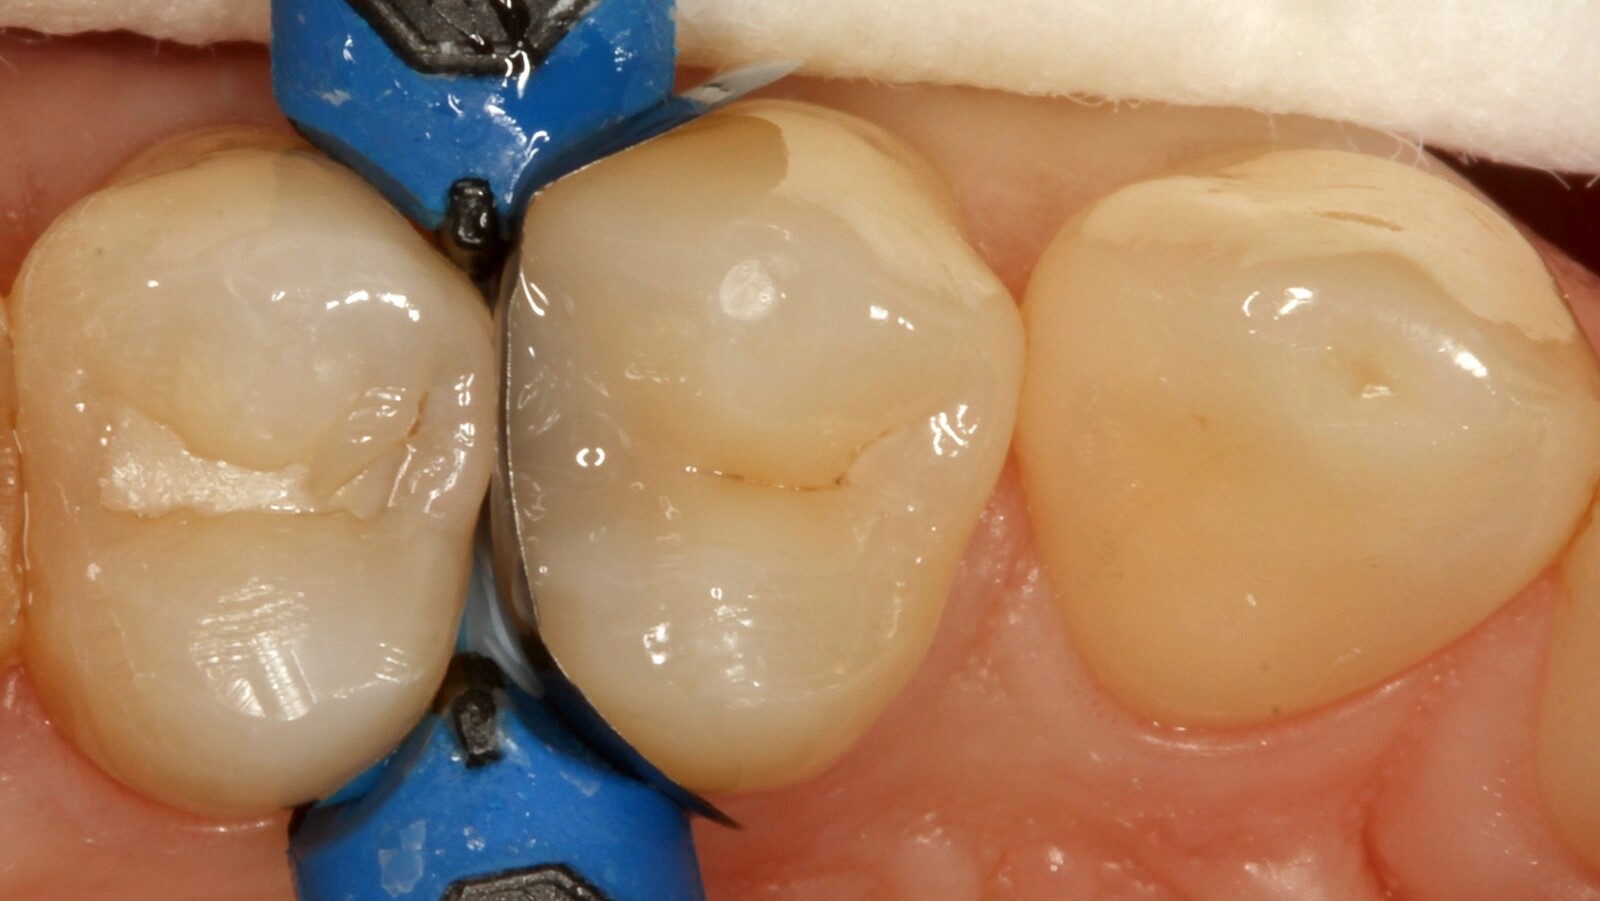

Professor Ernst identifizierte zunächst die versteckte Karies und öffnete die kariöse Läsion, um dem Patienten das Problem zu veranschaulichen (Abb. 1-2). Anschließend exkavierte er die Karies, präparierte die Kavität und setzte eine Teilmatrize ein (Abb. 3), bevor er die Kavität mit Adhäsiv versiegelte (Abb. 4). In einem einzigen Schritt füllte er die Kavität mit Venus Bulk Flow ONE (Abb. 5). Nach der Fertigstellung polierte Prof. Ernst die Restauration (Abb. 6) und fertigte ein Kontrollröntgenbild an, das ebenfalls die hervorragende Röntgenopazität von Venus Bulk Flow ONE zeigt (Abb. 7).